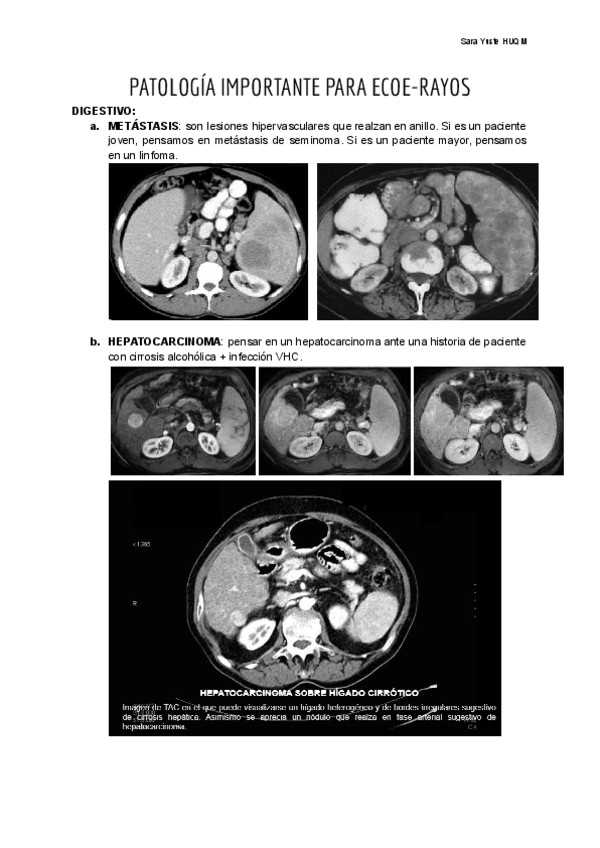

Patología + importante a saberse de cara a la estación de rayos del ECOE